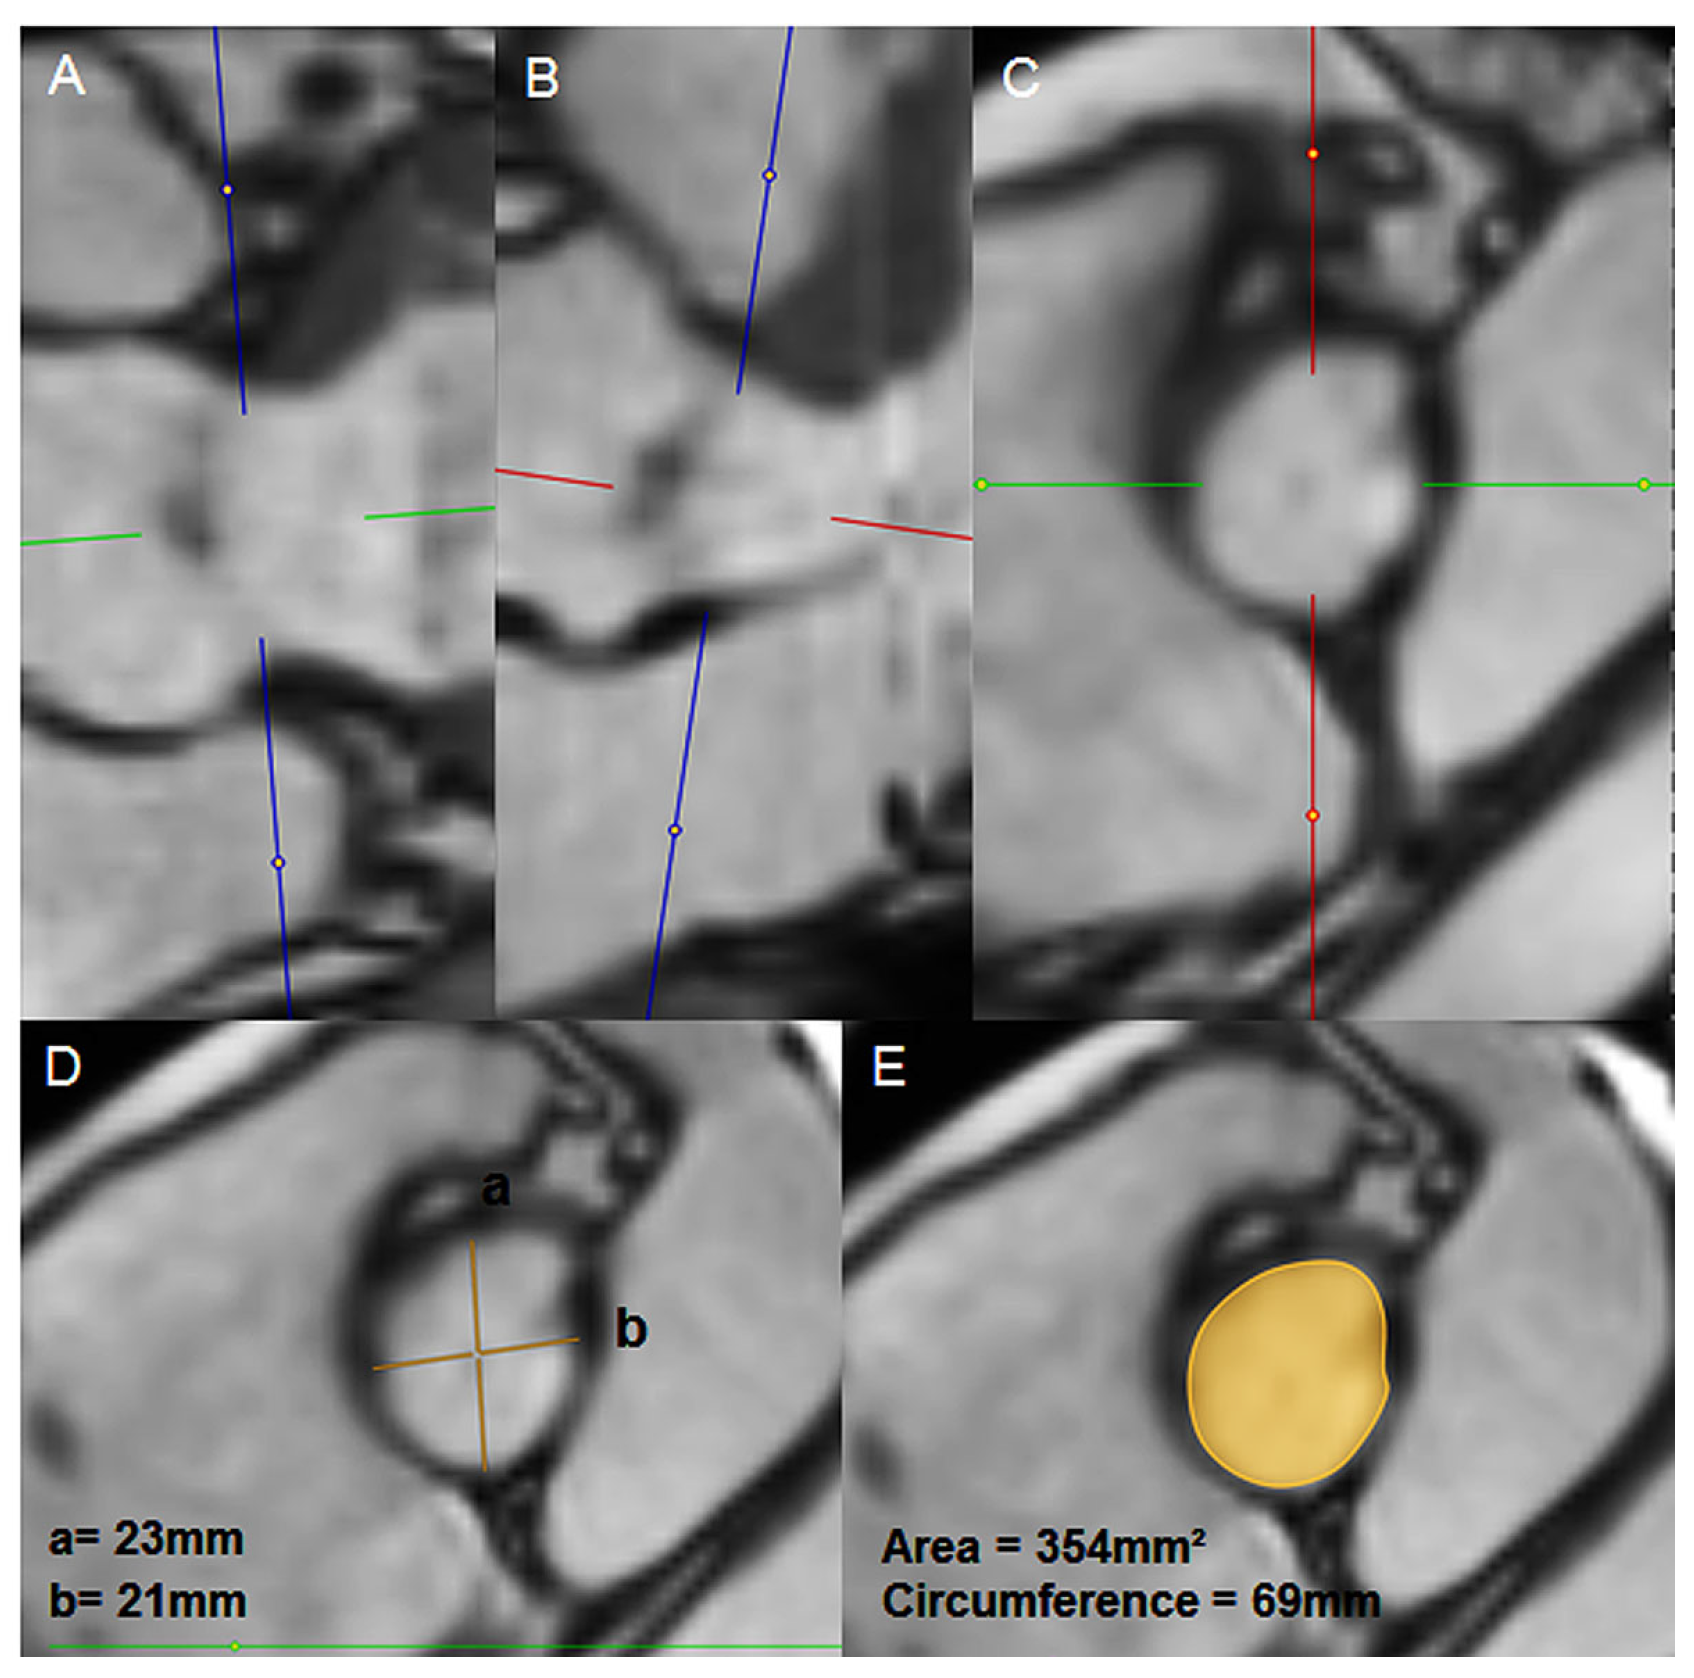

- Bernhardt, P.; Rodewald, C.; Seeger, J.; Gonska, B.; Buckert, D.; Radermacher, M.; et al. Non-contrast-enhanced magnetic resonance angiography is equal to contrast-enhanced multislice computed tomography for correct aortic sizing before transcatheter aortic valve implantation. Clin Res Cardiol. 2016, 105, 273–278. [Google Scholar] [CrossRef] [PubMed]